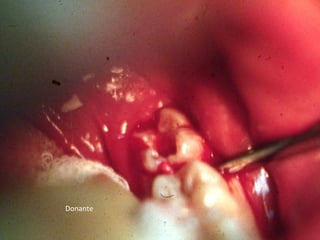

Receptor

Donante

Receptor momento de trasplante

Trasplante 3 meses de evolución